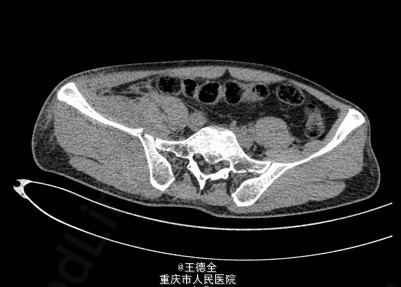

患者男性,51岁,因“高坠伤致左腰部及右髋部疼痛伴活动障碍3天”入院。急性痛苦面容,神志清楚,平车送入病房,右髋部软组织稍肿胀,局部皮肤完整,未见明显皮疹,挫擦伤及出血点.右股骨髁上骨牵引在位,左腰椎伴明显压痛,骨盆挤压实验阳性,可扪及骨擦音,骨擦感.双下肢感觉,活动,血循良好,足背动脉搏动好;右踝关节主动活动受限,被动活动正常。右侧各足趾背伸、跖屈活动正常,其余各关节活动正常。骨盆X线片示:右侧髂骨、髋臼、双侧耻骨上支、右侧耻骨下支多发骨折,左侧髂骨翼骨折,骨盆出入口右侧份形态失常。 初步诊断:右髋臼粉碎性骨折(Judet X 型) 诊疗计划:完善双下肢静脉彩超等检查;给予预防深静脉血栓、骨牵引治疗;给予止痛等对症支持治疗;密切观察病情变化,根据病情及时处理。